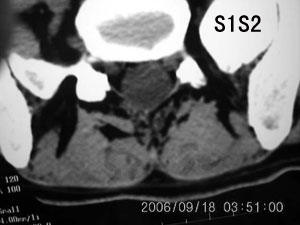

以下是引用守望可可西里在2006-9-18 21:29:00的发言:[br][br] 马尾肿瘤,密度较低,大部分似乎呈囊性变(看着很费眼),考虑室管膜瘤,建议mri。

以下是引用dyg在2006-9-18 22:27:00的发言:[br]正常脊髓.[br]分析:人的脊髓从枕大孔开始至腰1.2椎体为止,有2个生理膨大,分为颈膨大和腰膨大;该病人脊髓须然从腰段开始直至马尾似乎膨大,胆是与上段脊髓密度没有多大变化,所以我认为是正常膨大之延续;当然最好做ct增强或mri检查,排除肿瘤.

以下是引用飞虎在2006-9-18 20:18:00的发言:[br]部分椎管内密度不均且无ct值 故mri检查